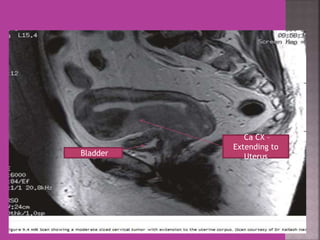

Ca CX –

Extending to

Bladder Uterus

Ca CX – Extending to Bladder Uterus